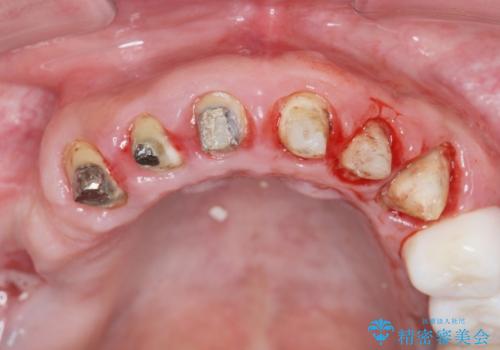

歯周組織検査を行うと歯ぐきからは容易に出血し、X線検査より歯とセラミッククラウンの適合が悪い(ピッタリと合っていない)状態が示唆され、歯ぐきの炎症を惹起している状態でした。

セラミッククラウンを除去し仮歯を装着し、歯周外科手術を行い歯ぐきの状態を改善したのち、適合の良いセラミッククラウンを再作製をする治療計画としました。